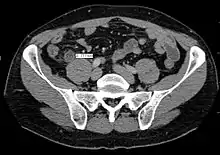

Инструментальное обследование

Ультразвуковое исследование — дилятация просвета (диаметр более 6 мм), отсутствие перистальтики, иногда может лоцироваться копролит. Ультразвуковое исследование должно быть первым инструментальным обследованием при подозрении на аппендицит. Обнаруживаются наполненная жидкостью, несжимаемая трубчатая конструкция с диаметром, превышающим 6 мм, аппендиколит, околоаппендикулярная перицекальная жидкость.

- Наиболее частый эхопризнак острого аппендицита — наличие свободной жидкости в правой подвздошной ямке (то есть, вокруг отростка) и (или) в полости малого таза (наиболее отлогом месте брюшной полости) — симптомы местного перитонита.

- Ультразвуковое исследование при остром аппендиците не всегда специфично. Для лоцирования (обнаружения) червеобразного отростка требуются: наличие обтурации отростка, опыт и аппарат экспертного класса. При гангренозно-перфоративном аппендиците, содержимое отростка изливается в брюшную полость, дилятация исчезает, отросток может не лоцироваться. Вместе с тем, обязательно лоцируется свободная жидкость в брюшной полости, может лоцироваться «свободный газ» в брюшной полости, паретичные петли тонкой кишки.

Усложняют ультразвуковое исследование кишечные газы, ожирение, защитная фиксация, движения. Обнаружение нормального аппендикса при ультразвуковом исследовании является основанием для исключения аппендицита.

Компьютерная томография информативна при наличии спирального томографа, когда выявляется обтурация червеобразного отростка, расширение его просвета, утолщение стенки (> 1 мм) признаки свободной жидкости (воспалительного выпота) в брюшной полости.